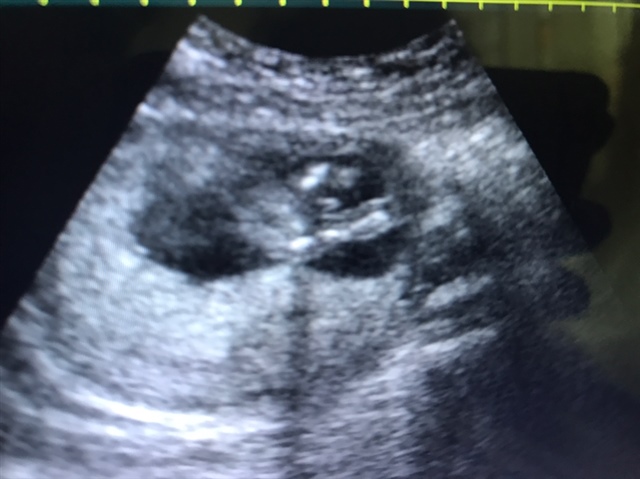

宝宝21天

是小鸡鸡,我检查男孩就是这样的

TST😘Monstar🐶(招代理)[帖主]:真的吗?我又怕不是,一个医生说是男的,一个说是女的,好迷茫

这是系带吧

TST😘Monstar🐶(招代理)[帖主]:我也不知道啊,我也好迷茫

是男的

TST😘Monstar🐶(招代理)[帖主]:怎么看的

几周做的

TST😘Monstar🐶(招代理)[帖主]:14周